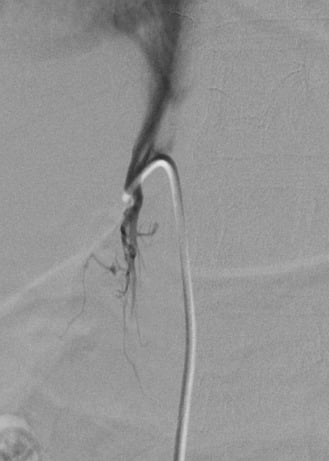

4.1. Bilateral Inferior Petrosal Sinus Sampling for Cushing’s Disease

- Deipolyi, A.R.; Alexander, B.; Rho, J.; Hirsch, J.A.; Oklu, R. Bilateral inferior petrosal sinus sampling using desmopressin or corticotropic-releasing hormone: A single-center experience. J. Neurointerv. Surg. 2014. [Google Scholar] [CrossRef] [PubMed]

- Deipolyi, A.; Bailin, A.; Hirsch, J.A.; Walker, T.G.; Oklu, R. Bilateral inferior petrosal sinus sampling: Experience in 327 patients. J. Neurointerv. Surg. 2016. [Google Scholar] [CrossRef]

- Oldfield, E.H.; Doppman, J.L.; Nieman, L.K.; Chrousos, G.P.; Miller, D.L.; Katz, D.A.; Cutler, G.B., Jr.; Loriaux, D.L. Petrosal sinus sampling with and without corticotropin-releasing hormone for the differential diagnosis of Cushing’s syndrome. N. Engl. J. Med. 1991, 325, 897–905. [Google Scholar] [CrossRef] [PubMed]